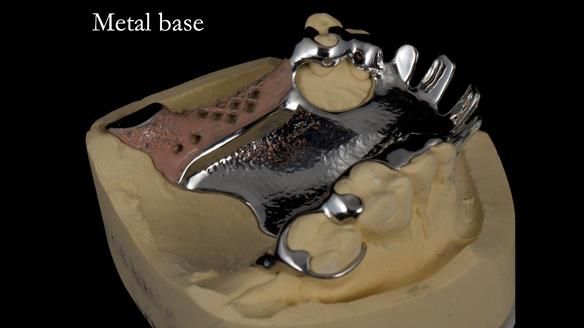

Keith’s case was one of the most challenging and rewarding cases I’ve treated this year. This 64 year old man presented with ill-fitting acrylic partial dentures that lacked stability, retention, and aesthetics. They constantly broke. He had lost the upper front teeth in a road traffic accident in his early 20s. The unopposed teeth had erupted, taking up space. After careful planning, we made a durable, metal-based upper partial denture/splint to address his dental concerns. He loved the outcome.

1. Denture design: A custom cobalt-chromium framework was Scandinavian-designed to maximise stability, protect the remaining teeth, and allow for future additions if needed.

Keith’s denture incorporated a Duracetal shell clasp on upper right first premolar (Myerson), which are designed to be virtually visible, providing a more aesthetic solution while enhancing patient comfort. The Scandinavian-inspired approach, based in modern removable prosthodontic techniques, ensured the denture was not only durable but also visually pleasing. Additionally, the design was carefully planned to allow for future modifications, ensuring that if Keith loses additional teeth, the denture can be adapted rather than replaced entirely.